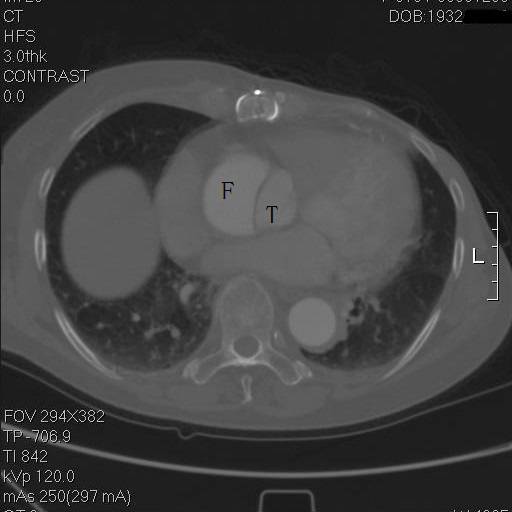

某友分享了这么一组影像图片。

患者是一例A型主动脉夹层,上图中F示假腔,T示真腔,这没什么奇怪。但仔细一看,胸骨的边缘具有高密度影,中间还有一小片低密度区,这例病例接受过前胸正中开胸的手术。

是的,回顾其病史,她一年半前,罹患A型主动脉夹层,第一内膜破裂口在右冠上方,夹层延续到弓部,在弓上分支开口处撕裂形成了出口,她接受了一种显得有些奇怪的术式。

往上阅片,假腔内竟然有一个支架影!